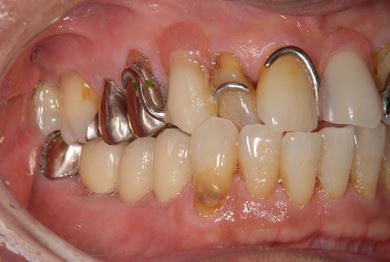

| 性別/年齢 | 男性 / 65歳 | ||||||||||||||||||||||||||||||||

| 主訴 | 右奥歯の義歯の不具合について相談したい。 | ||||||||||||||||||||||||||||||||

| 治療方針 | 抜歯と同時にインプラント埋入を行い、治療期間を短縮する。 | ||||||||||||||||||||||||||||||||

| 治療内容 | インプラント5本(抜歯即日スピードインプラント、テンポラリーインプラント)、メタルボンドセラミッククラウン5本 | ||||||||||||||||||||||||||||||||

| 総治療費 | 1,913,100円 | ||||||||||||||||||||||||||||||||

| 治療期間 | 1年9ヶ月 |